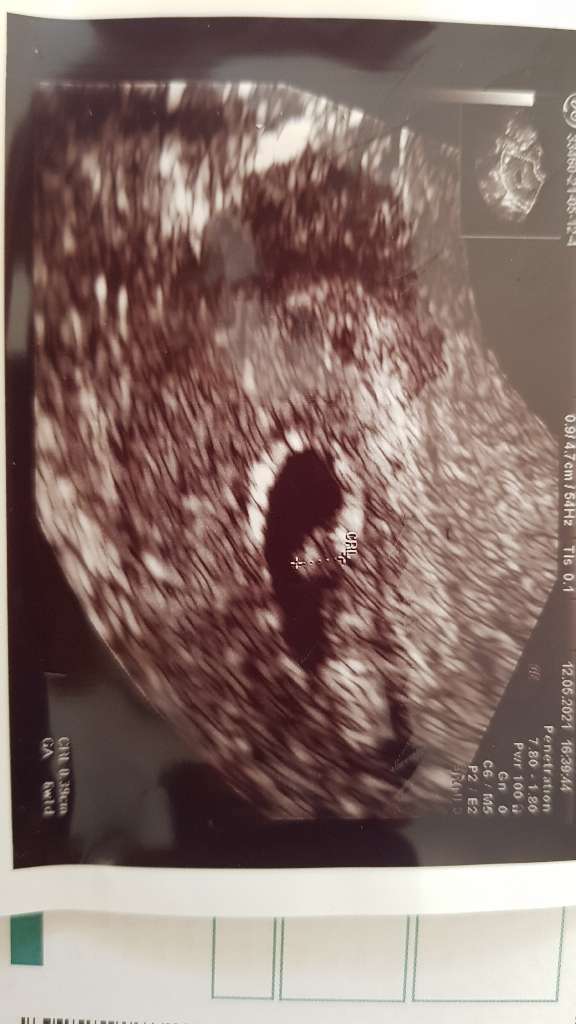

Dziewczyny jestem 5 + 4 i nic nie widać. Tzn mówił że jest pulsujące miejsce i tam powinno być serduszko. Ale był dzisiaj taki zawieszony, że sama nie wiem. Pokażę Wam zdjęcie.

Kazał powtórzyć betę i zrobić przyrost. Plus inne badania, za tydzień założy kartę ciąży, jeśli będzie wszystko ok.

Na zdjęciu jakby było już coś. Sama nie wiem